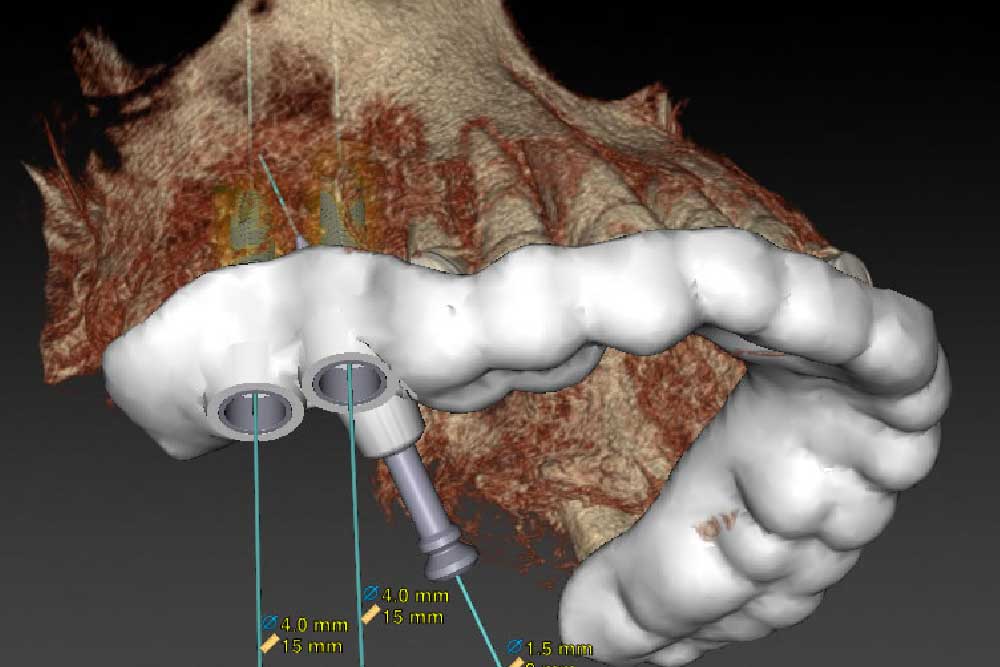

CT精密検査・事前シミュレーションの徹底

インプラント治療では、事前にCTによる精密検査を行い、顎骨の高さ・厚み・密度をはじめ、周囲の血管や神経、上顎洞の位置などを3次元画像で詳細に確認します。

得られたデータをもとに、埋入位置・角度・深さを事前にシミュレーションし、リスクを十分に考慮したうえで適切な治療計画を立案いたします。

サージカルガイドの使用で人為的ミスを防止

インプラント手術では、CTデータとシミュレーションをもとに作製した「サージカルガイド」を使用します。

サージカルガイドには、インプラントの理想的な埋入位置・角度・深さ(最終到達点)が反映されているため、人為的なミスを防止し、神経や血管への影響を最小限に抑えることができます。